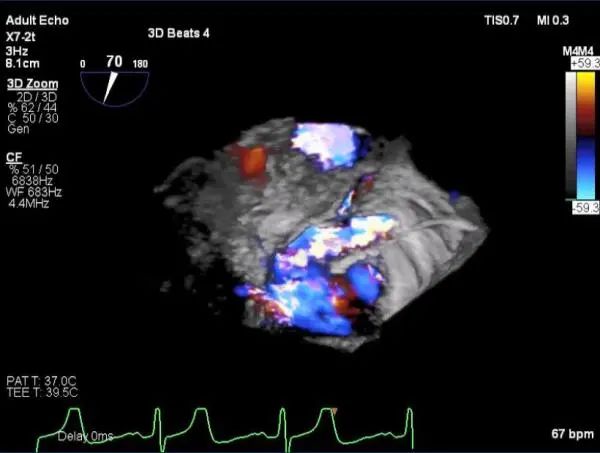

三维超声心动图显示第一枚XTR夹子释放,残余返流主要位于外侧

第二枚XTR夹子释放,返流明显减少

三维超声心动图显示第二枚XTR夹子释放